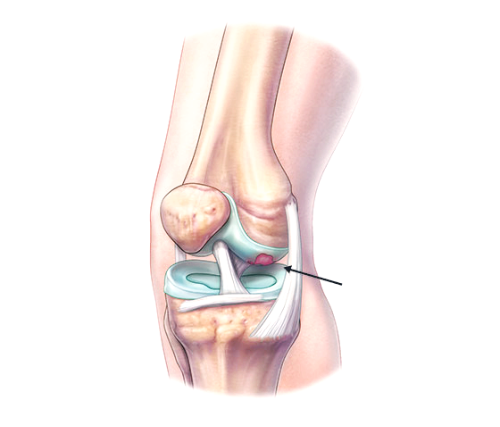

골관절염은 연골에 손상이 가해지면서 관절의 간격이 줄어들고 뼈가 서로 맞닿아 통증을 동반하는 질병입니다. 콘드로이친은 질병과 외부 충격으로부터 체내의 조직을 안전하게 보호하고 동시에 조직 표면에 가해지는 충격 등을 이겨낼 수 있도록 탄성을 주는 프로테오글리칸(Proteoglycan)이라는 물질의 생성을 돕게 됩니다. 때문에 콘드로이친은 특히 골관절염에 효과가 있습니다.

콘드로이틴황산염은 연골 구성 성분의 하나이고 연골세포를 자극해 연골조직을 정상적으로 복원하는데 효능이 있다고 알려져 있습니다. 특히 외부 자극에 의해 문제가 되는 TNF-알파 등 사이토카인의 작용을 억제하는 역할을 합니다. 그리고 지속적인 염증 유발 및 연골 파괴 유발 사이토카인을 감소시켜 관절 내 염증 및 통증반응 그리고 연골파괴를 막아주는데 도움을 줍니다.

콘드로이친은 연골에 보습 및 탄력을 공급하려 상처 난 연골을 정상적으로 재생시키는 효과가 있습니다. 콘드로이친을 섭취하게 되면 무릎이나 허리 등의 관절염으로 인한 통증을 완화시킬 수 있습니다.

콘드로이친은 글루코사민과 같이 연골 성분의 일부로써 연골, 힘줄, 뼈, 각막 등의 신체 결합 주위에 널리 퍼져 있습니다. 관절 연골에 필요한 영양을 공급하고 연골을 분해하는 효소를 억제함으로써 관절 건강에 도움을 줍니다.